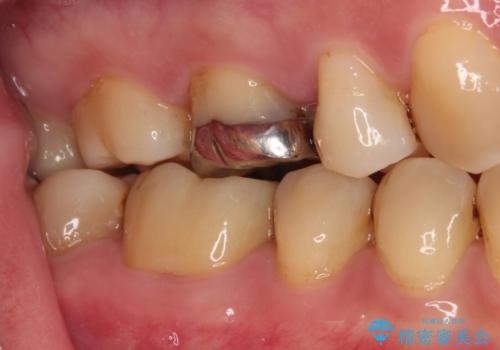

- 人と話す際に、下顎の奥にある銀歯が目立って気になるとのことで来院された患者様です。

左右の奥歯に銀歯のクラウンが装着されていたため、銀歯除去後に仮歯に置き換え、フルジルコニアクラウンにて補綴治療を行うこととしました。

フルジルコニアクラウンは、やや光沢のある材質ですが、奥歯に装着した場合にはさほど気にならず、自然な口元の印象となりました。